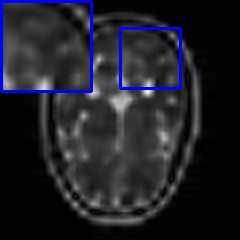

Limited by imaging systems, the reconstruction of Magnetic Resonance Imaging (MRI) images from partial measurement is essential to medical imaging research. Benefiting from the diverse and complementary information of multi-contrast MR images in different imaging modalities, multi-contrast Super-Resolution (SR) reconstruction is promising to yield SR images with higher quality. In the medical scenario, to fully visualize the lesion, radiologists are accustomed to zooming the MR images at arbitrary scales rather than using a fixed scale, as used by most MRI SR methods. In addition, existing multi-contrast MRI SR methods often require a fixed resolution for the reference image, which makes acquiring reference images difficult and imposes limitations on arbitrary scale SR tasks. To address these issues, we proposed an implicit neural representations based dual-arbitrary multi-contrast MRI super-resolution method, called Dual-ArbNet. First, we decouple the resolution of the target and reference images by a feature encoder, enabling the network to input target and reference images at arbitrary scales. Then, an implicit fusion decoder fuses the multi-contrast features and uses an Implicit Decoding Function~(IDF) to obtain the final MRI SR results. Furthermore, we introduce a curriculum learning strategy to train our network, which improves the generalization and performance of our Dual-ArbNet. Extensive experiments in two public MRI datasets demonstrate that our method outperforms state-of-the-art approaches under different scale factors and has great potential in clinical practice.